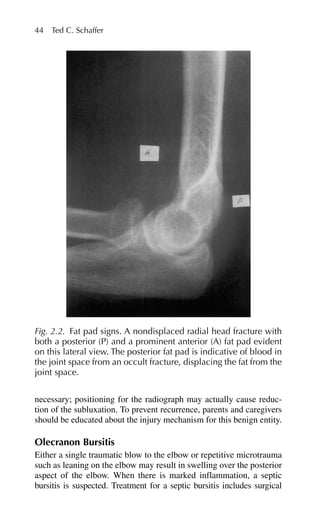

joints. The ultimategoal is to utilize these various treatments to encourage children with JRA to live active, normal lives. The family physician coordinates care with other members of the treatment team and offers necessary support to the child and family. Systemic Lupus Erythematosus Systemic lupus erythematosus (SLE) is a complicated rheumatological disorder with a broad range of presentations. The incidence of SLE has more than tripled in the past 30 years, from 1.5/100,000 in 1950–79 to 5.6/100,000 in 1980–92.18 The incidence among female patients is three times that of male patients, resulting in a prevalence of 1 in 700 for women between the ages of 20 and 64 years.19,20 The disease incidence in African-American and Hispanic women in the same age group is higher than in their Caucasian counterparts. The pathogenesis of SLE is not completely understood. Current theories include polyclonal B-cell activation and antigen stimulation resulting in the immune response that characterizes this complex dis- order. Studies have pointed to a genetic factor contributing to the development of SLE. Twin studies have revealed a concordance rate among monozygotic twins to be as high as 30% to 50%. An associa- tion with human leukocyte antigen (HLA) groups DR2, DR3, DR4, and DR5 has also been found. Laboratory Findings Detection of antinuclear antibodies is a highly sensitive screening test for SLE, although it is not specific for SLE. A marginally elevated anti- nuclear antibodies titer is found in 2% to 5% of normal individuals.20 About 95% of SLE patients have positive antinuclear antibodies titers that are more than two times higher than the normal limit identified by any given laboratory. Other antibodies identified in SLE patients include anti-double-stranded DNA, anti-DNA-histone complex, anti- Sm (Smith antigen), and anti-Ro (Robert antigen). Antibodies to dsDNA and Sm antigen are specific for SLE and have been associated with more severe cases. Anti-Ro antibodies are associated with various dermatological manifestations of SLE. Anti-single-stranded DNA is not specific for SLE and therefore plays no role in diagnosis. Up to 30% of SLE patients also have circulating antiphospholipid antibodies. These antibodies, known as the “lupus anticoagulant” may result in prolonged partial thromboplastin (PTT) and prothrombin (PT) times yet paradoxically result in an increased risk of thrombotic events. When counseling female patients who have circulating 5. Rheumatoid Arthritis and Related Disorders 113

• 128.

antiphospholipid antibodies, itis important to discuss the increased risk of spontaneous abortions. In fact, a history of recurrent sponta- neous midtrimester abortions should trigger testing for antiphospho- lipid antibodies. Systemic lupus erythematosus is characterized by a wide variety of presentations. The SLE classification system, revised in 1982 and updated in 1997, identifies 11 symptoms of the disease or systems affected in SLE patients. To confirm a diagnosis of SLE, patients must have at least 4 of the 11 criteria present either serially or simultane- ously (Table 5.4). Mucocutaneous Manifestations The classic malar butterfly rash is present in only one third of patients. It usually presents abruptly after exposure to sunlight and lasts for several days or weeks. More commonly, patients have a patchy macu- lopapular rash on sun-exposed areas. Subacute cutaneous lupus erythe- matosus presents with a unique rash characterized by photosensitivity and superficial, nonindurated, nonscarring lesions. One third to two thirds of SLE patients are markedly photosensitive, and sun exposure not only results in rash but also may induce a flare of systemic manifestations. Seventy percent of patients with photosensi- tivity have anti-Ro antibodies.21 Discoid lesions are raised plaques that may result in scarring. Other skin manifestations include alopecia, hyperpigmentation, and hives. Biopsy shows immunoglobulin deposition at the dermoepidermal junction. This finding is known as the lupus band test.22 Arthritis Arthralgias are the most common complaint of SLE patients and are often present at the time of initial diagnosis. Up to 76% of patients develop arthritis associated with disease activity. It is difficult to dif- ferentiate the joint complaints of SLE patients from those of RA patients, but SLE patients usually present with pain out of proportion to the degree of synovitis. Also, in contrast to RA patients, SLE patients have soft tissue involvement that can result in joint deformity without evidence of cartilage involvement (Jaccoud arthropathy). Tendon rupture can also occur. Serositis SLE patients can have inflammation of the pleural, pericardial, and peritoneal membranes. Exudative pleural effusions are common but 114 Joseph W. Gravel Jr., Patricia A. Sereno, Katherine E. Miller

• 129.